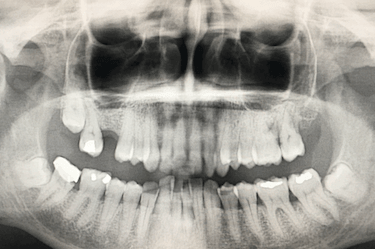

Caso de implantes dentales sin hueso suficiente y regeneración ósea

Paciente real del Dr. Ferrer que presenta la ausencia de una pieza dental.

Al no haber sustituido el diente perdido se ha producido una reabsorción ósea que ha provocado una disminución de la altura del hueso maxilar.

Antes del injerto de hueso dental solo había una altura de 5 mm para colocar el implante.

Para que el especialista pueda colocar un implante dental de forma estable y segura, es necesario una altura de hueso maxilar de al menos 8 – 10 mm.